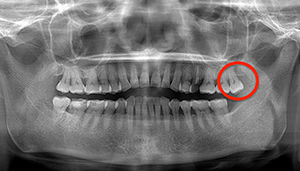

CT

- Before

- After

CTで親知らずと神経(下歯槽管)の位置を確認しました。

親知らずと神経は一定の距離があり、麻痺などのリスクがほとんどないと判断できます。

口腔内

半埋伏の親知らずでした。3糸縫合しました。